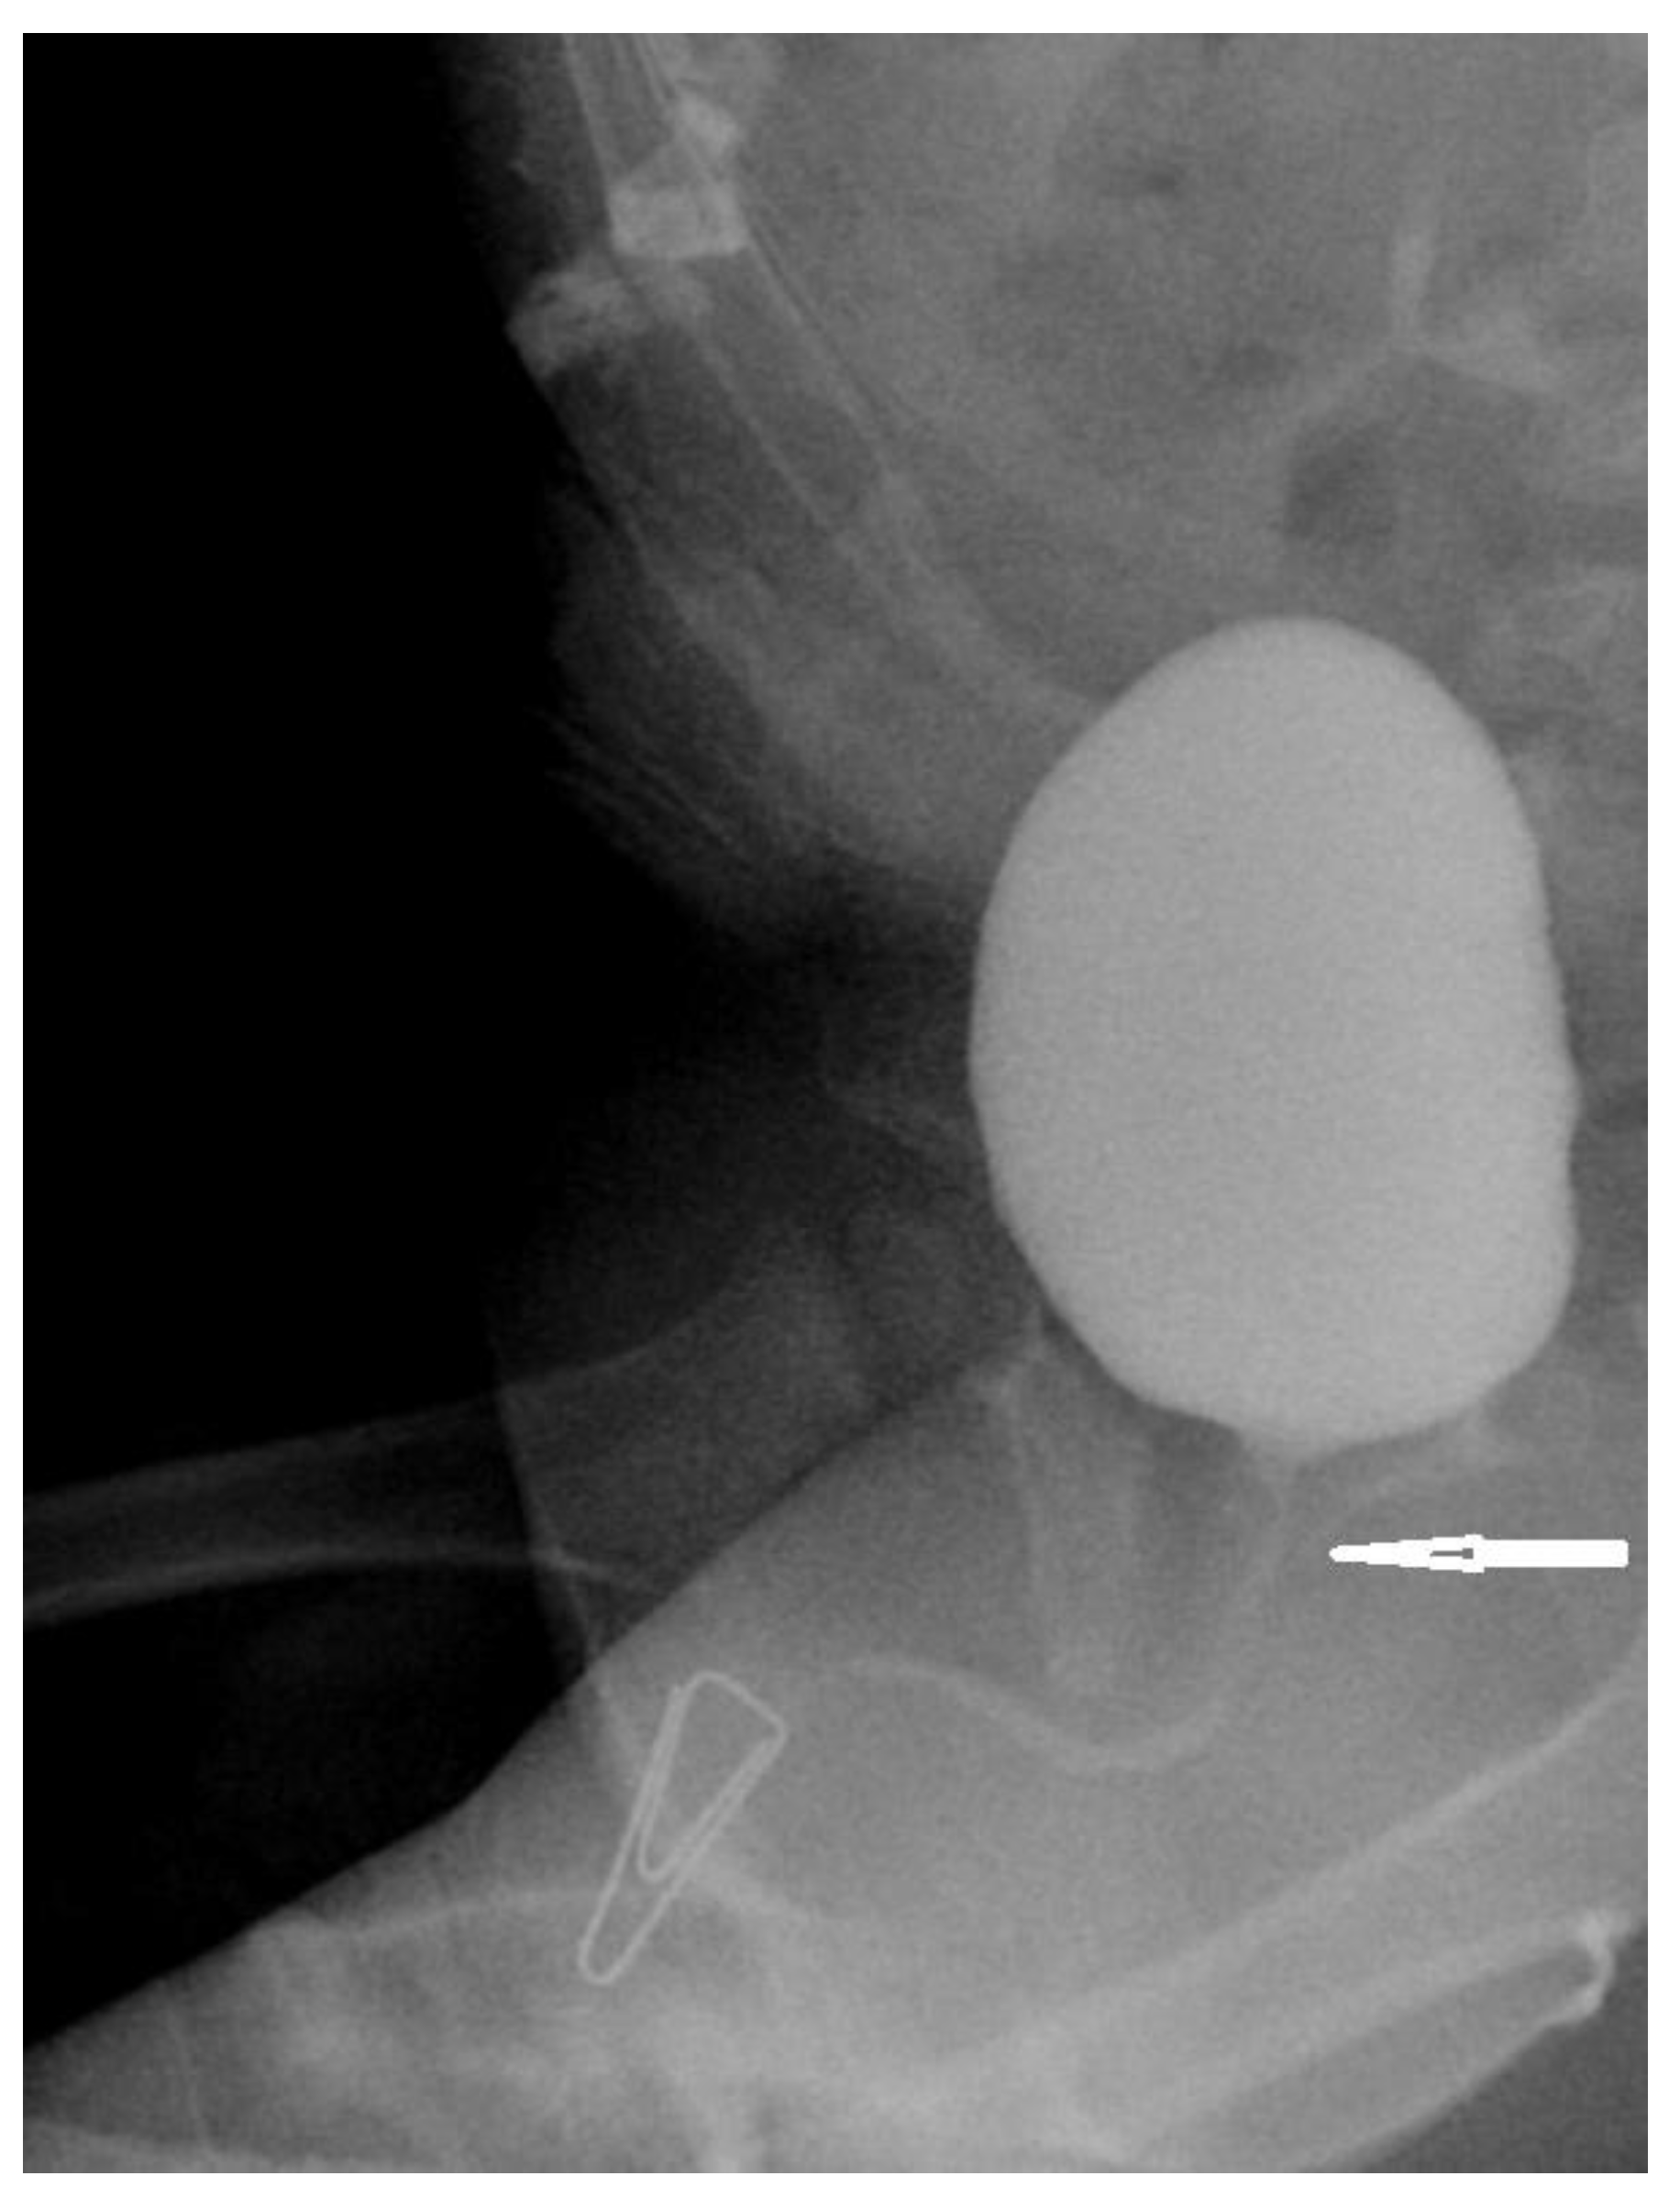

2.2. Surgical Procedures